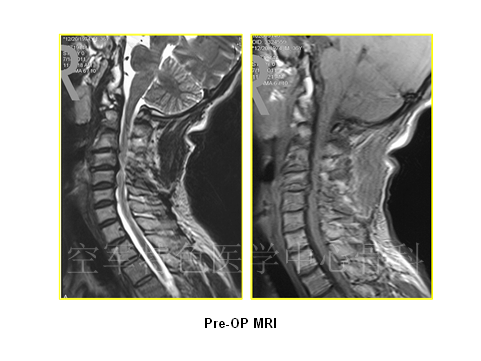

患者男性,37岁,主诉:头颈部不停抽动11年,四肢麻木无力,行走不稳 1月余。既往曾以“共济失调”入住神经内科。查体:颈3平面以下痛觉减退,双肘关节以下痛觉减退明显,胸4平面以下感觉减退。四肢肌力Ⅳ级,四肢腱反射活跃,肌张力高。双侧Hoffman’s征+,Babinski’s征+。JOA评分:9分。患者入院时头颈部不自主的扭动,行走不稳,易摔跤。

患者影像学资料如下: